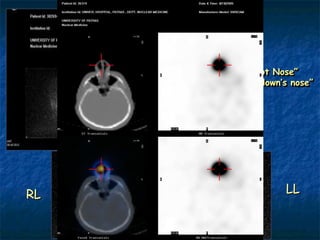

“Hot Nose”

“The clown’s nose”

RL              LL